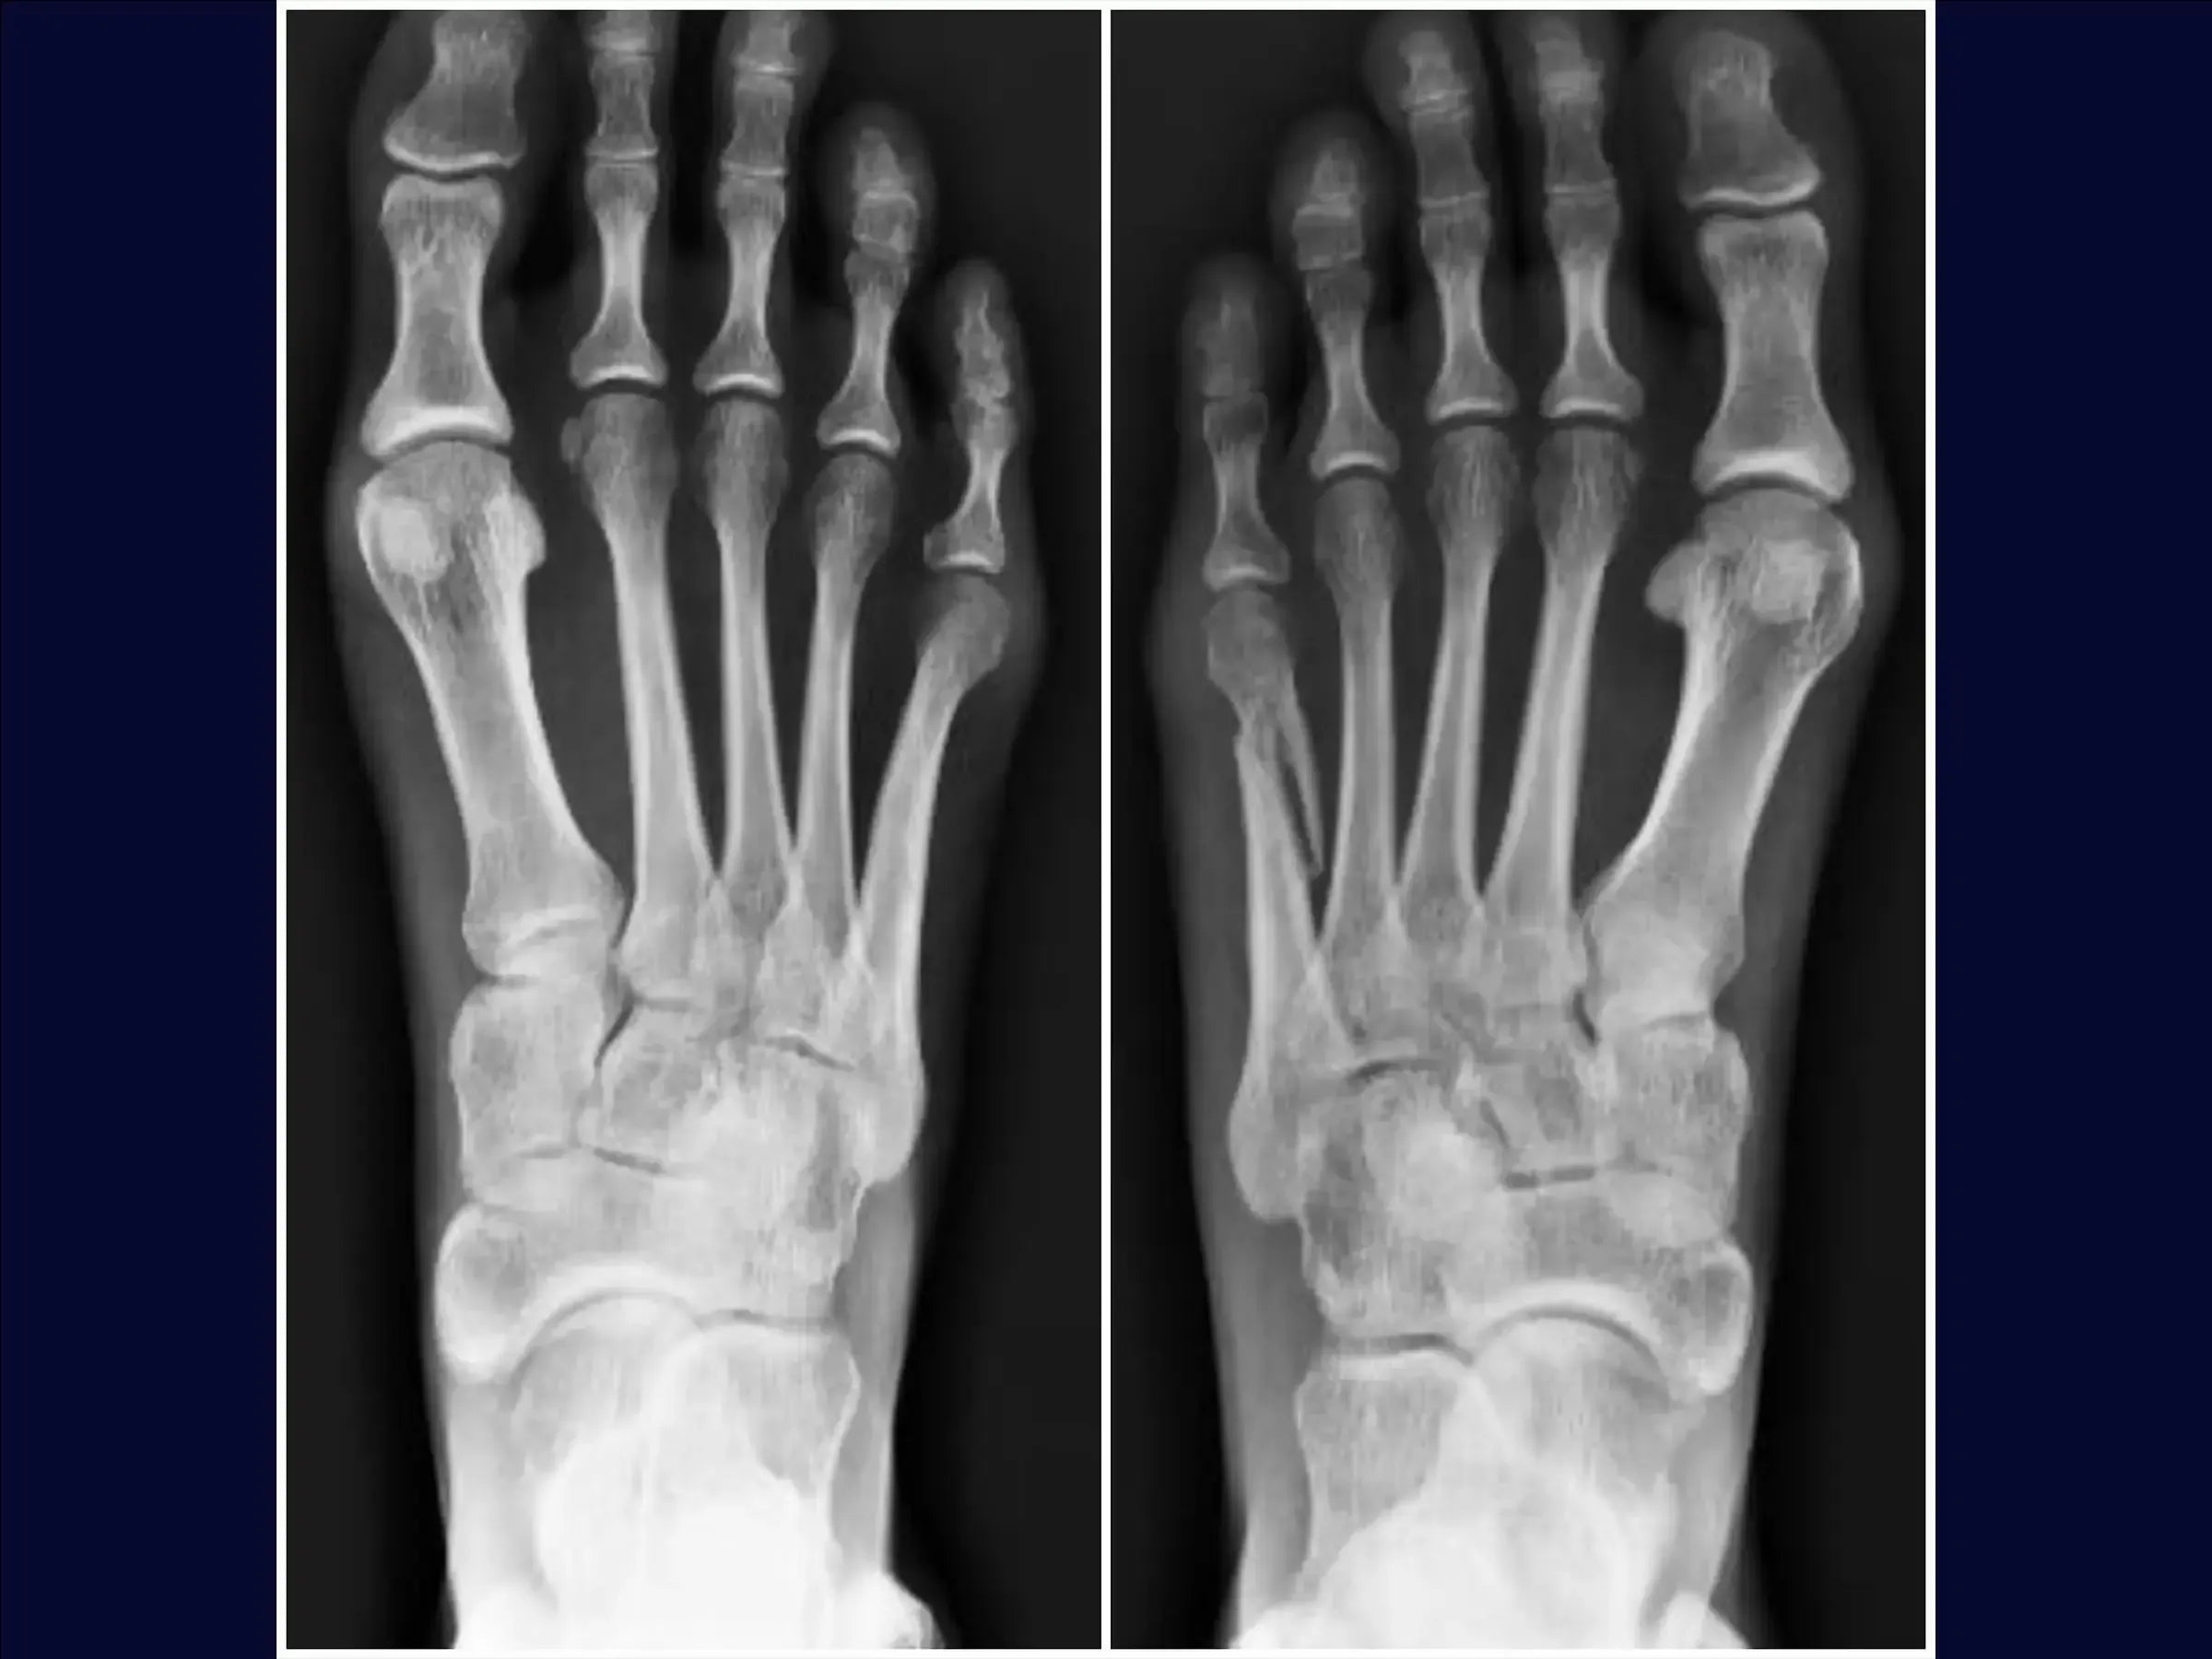

Fractura desplazada del quinto metatarsiano

Mejore sus habilidades en el tratamiento quirúrgico de fracturas desplazadas del quinto metatarsiano. Este procedimiento requiere una reducción anatómica cuidadosa para evitar la metatarsalgia o la disfunción de la marcha, especialmente en pacientes jóvenes y atletas. Esta capacitación detalla el procedimiento quirúrgico con placa de bloqueo y tornillos, con énfasis en la rápida recuperación funcional y el retorno a la actividad deportiva.

- Evaluación y planificación del acceso: análisis de radiografías para identificar la angulación de la fractura y la posibilidad de alteración de la carga de peso, metatarsalgia o disfunción de la marcha.